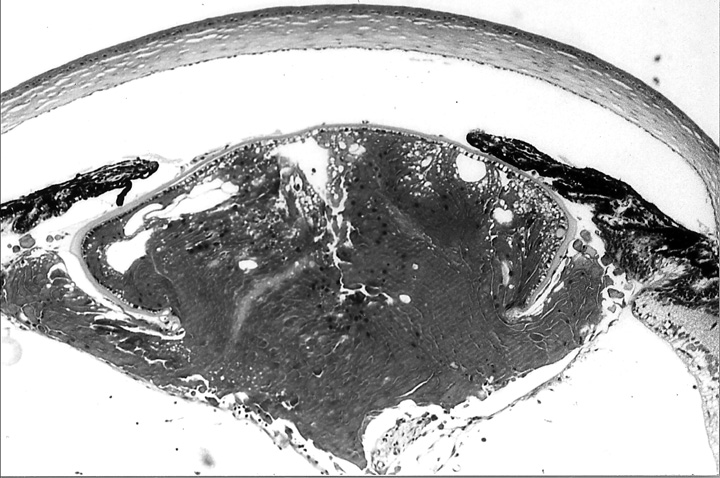

Figure 1d. Higher power view of lens in Fig. 1c.

The lens has a nucleus with non-nucleated fibers, but these are disorganized.